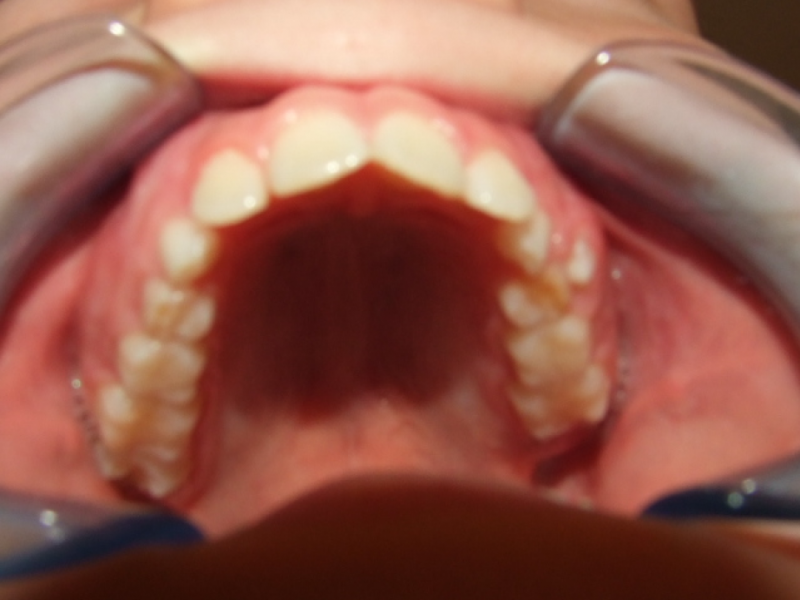

Behandeling Raoul

Duur

van 13-3-14 tot 16-9-15

Beschrijving

Leeftijd bij aanvang: 10 jaar

Bonded Hyrax + volledig vast onderkaak

Volledig vast bovenkaak + expander

Wrap + c-c bar onderkaak

Leeftijd bij afname: 12 jaar

Voor behandeling

Na behandeling